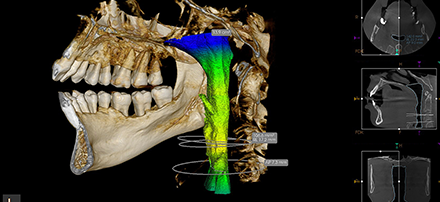

• IMÁGENES 3D DE ALTA RESOLUCIÓN SIN RUIDO

A 75 micras, el sistema de CS 8200 3D ofrece imágenes de ultra alta resolución idóneas para aplicaciones de endodoncia, así mismo, el algoritmo ANR reduce el ruido de la imagen sin perder detalles clínicos.